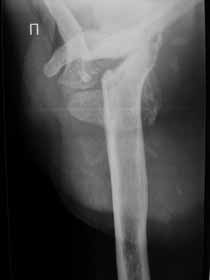

Поэтому желательно выставить все рентгенологические и данные МРТ для сравнения со снимками из статьи.

Думаю, коллеги будут не против увидеть рентген.

Извиняюсь, что-то фотографии сразу не прошли. сейчас исправимся.